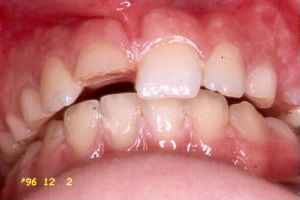

Michaela kom till kliniken 961202 med komplicerad

kronrotfraktur med pulpablotta på 11. Hon ramlade och slog sig tre dagar innan och tanden

har stått öppen sen dess.

961202